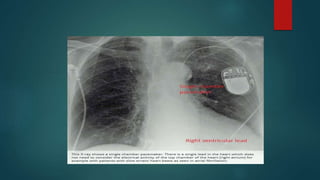

Single Chamber Ventricular Pacing

(VVI, VVT)

 VVI is the most widely used form of pacing in which ventricle is sensed and

paced.

 It senses the intrinsic R wave and thus inhibits the pacemaker function.

Indication- complete heart block with chronic atrial flutter, atrial fibrillation

CHEST X-RAY

Lead position

Paced position

Type of CIED